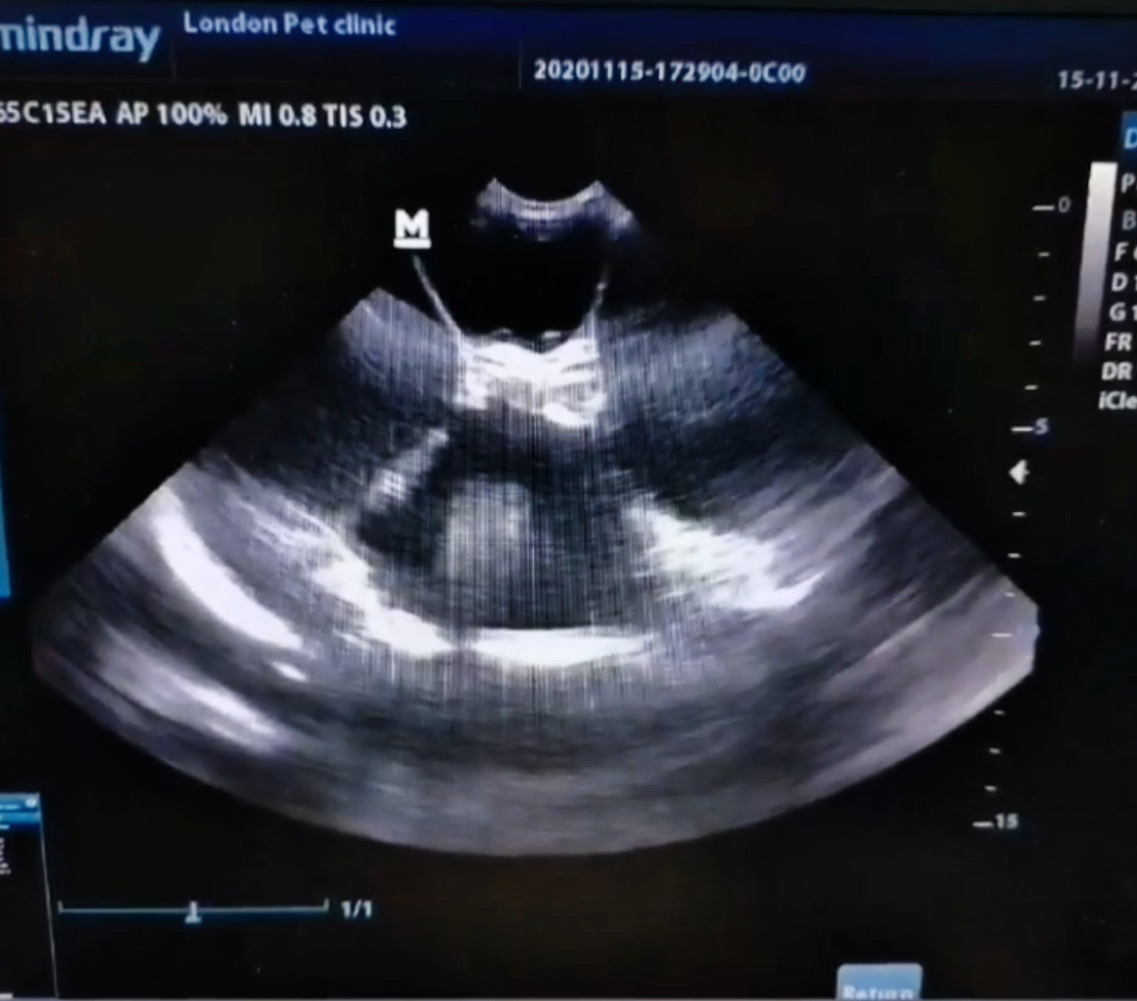

Abdominal Ultrasound

• Enlarged, fluid-filled uterus

• No visible fetuses or placental structures

• Fluid is anechoic, consistent with hydrometra (watery fluid)